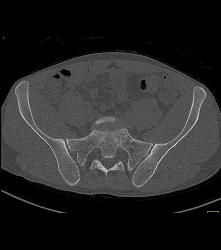

Subtle Cystic Lesion S-1 That Was Metastatic